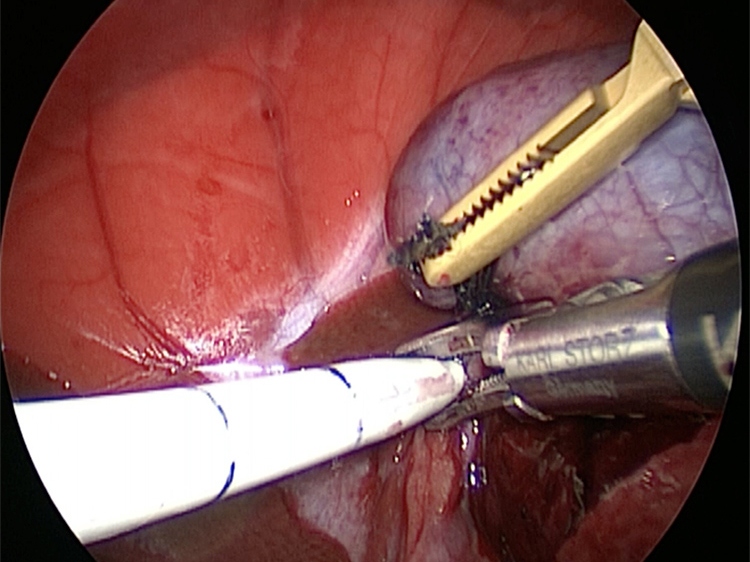

お腹にトロッカーを4本挿入し、そこから鉗子とカメラを入れて胆嚢を肝臓から剥がしていきます。 カメラで拡大しながら見ることができるので開腹手術よりも視野が確保できます。

胆嚢の頸部に糸を通し動脈を確保しています。

胆嚢を少しずつ丁寧に肝臓から剥がしています。